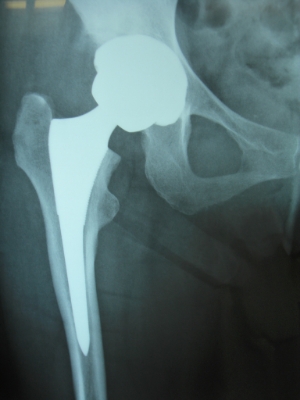

50歳 変形性股関節症 MIS-DAによる人工股関節置換術

術後3日目に歩行訓練開始し術後2週で杖なし歩行で退院

58歳 大腿骨頭壊死 MIS-DAによる右人工股関節置換術

術後2日で離床、3日めに歩行器歩行訓練開始、5日で杖歩行、7日で杖なし歩行可能となり2週で退院

86歳 続発性変形性股関節症 MIS-DAによる右人工股関節置換術

術後3週で杖歩行により退院